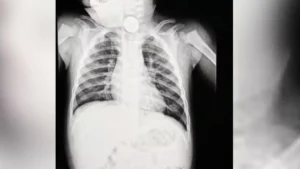

Pedro foi levado para atendimento médico, onde um exame de raio-x identificou um objeto no esôfago. Inicialmente, a suspeita era de que se tratava apenas de uma peça de algum brinquedo de plástico, o que fez com que o caso fosse tratado como menos urgente. Incomodados com a demora, os pais decidiram procurar outro serviço de saúde.

Após novos exames, os médicos confirmaram que o objeto era, na verdade, uma bateria tipo botão, semelhante às usadas em relógios. O item foi retirado por endoscopia depois de cerca de 12 horas no organismo da criança. Durante o procedimento, os profissionais identificaram sinais de necrose no esôfago e risco de perfuração, uma complicação grave que pode levar à infecção generalizada.